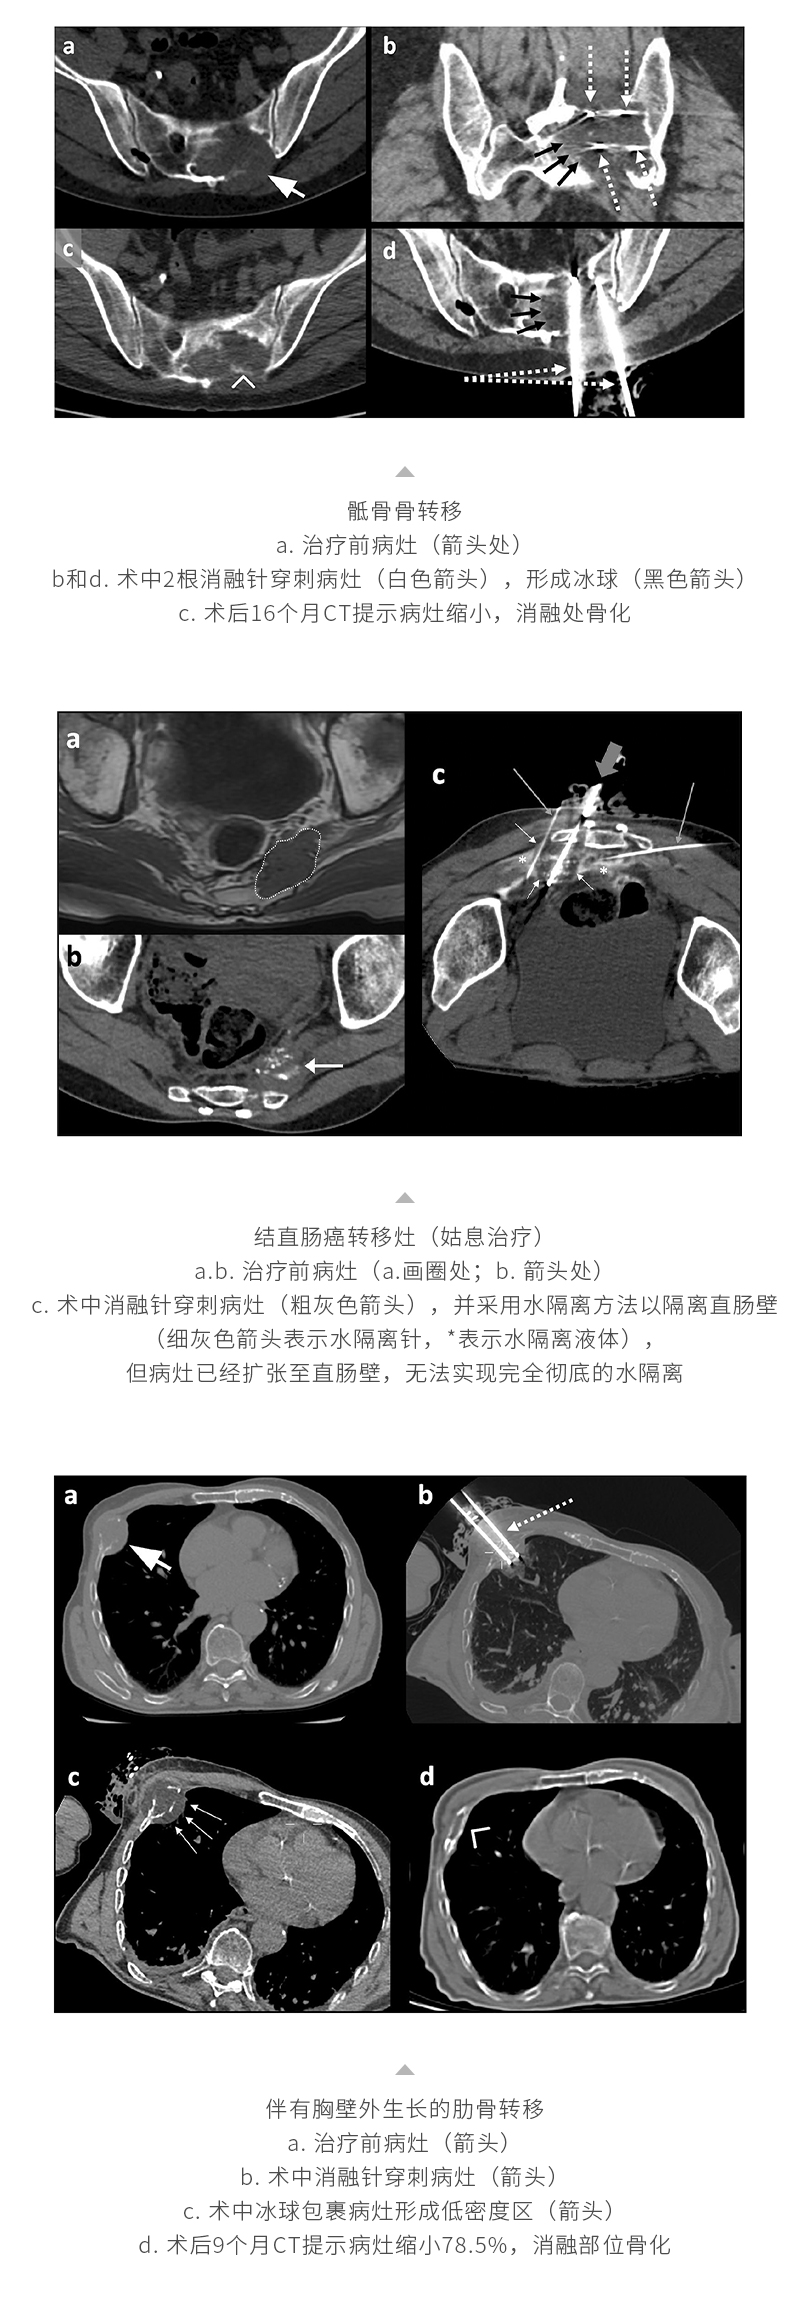

冷凍消融轉(zhuǎn)移性骨腫瘤——【海杰亞科研資訊】第268期